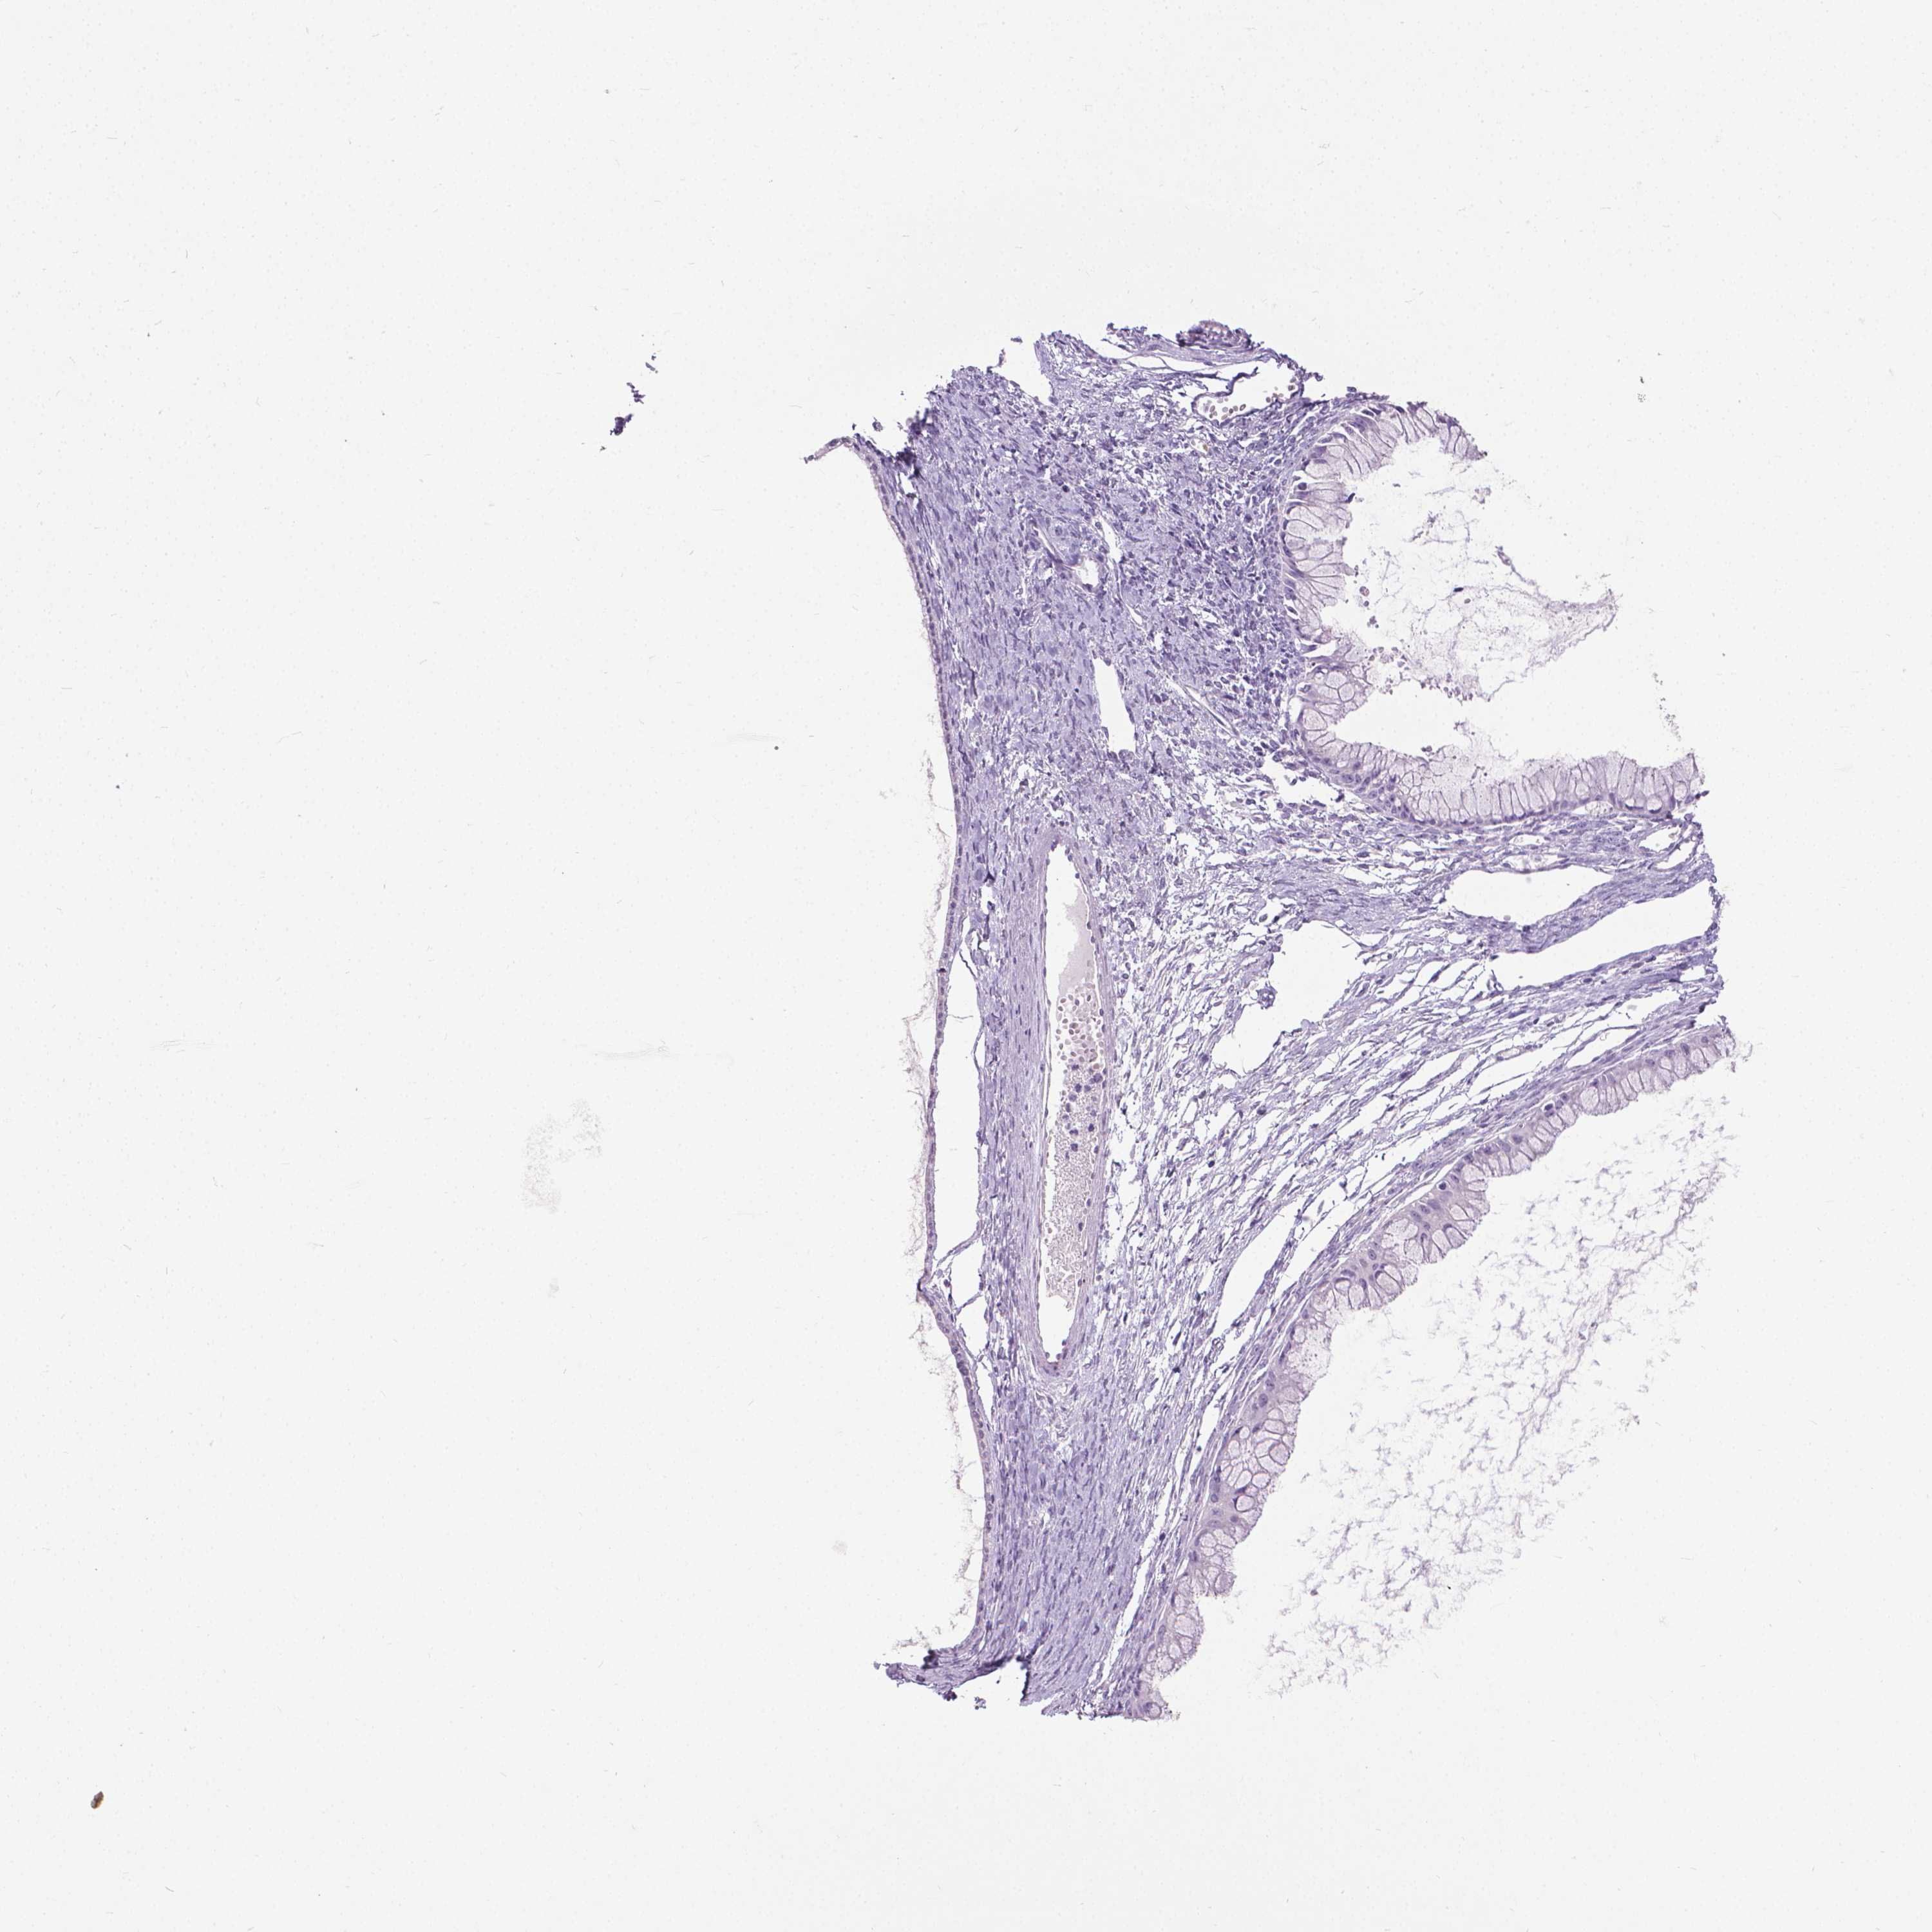

OVARIAN CANCER - Protein expressioni

A mouse-over function shows sample information and annotation data. Click on an image to view it in a full screen mode. Samples can be filtered based on level of antibody staining by selecting one or several of the following categories: high, medium, low and not detected. The assay and annotation is described here.

Note that samples used for immunohistochemistry by the Human Protein Atlas do not correspond to samples in the TCGA dataset.

Antibody stainingi

Antibody staining in the annotated cell types in the current human tissue is reported as not detected, low, medium, or high, based on conventional immunohistochemistry profiling in selected tissues. This score is based on the combination of the staining intensity and fraction of stained cells.

Each image is clickable and will lead to virtual microscopy that enables deeper exploration of all samples and also displays staining intensity scores, fraction scores and subcellular localization as well as patient and tissue information for each sample.

Antibody HPA059479

Antibody CAB000027

Cystadenocarcinoma, serous, NOS

Cystadenocarcinoma, mucinous, NOS

Carcinoma, endometroid